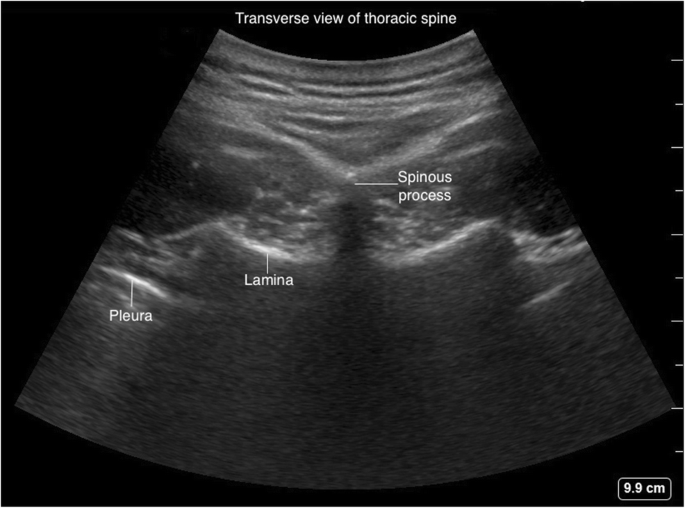

The upper thoracic (T1-T4) and lower thoracic (T9-12) vertebrae have similar geometry to cervical and lumbar vertebrae and amenable for US scanning (Fig. 19). The mid-thoracic (T5–T8) vertebrae have extreme inferior angulation of spinous process and pose technical challenges for ultrasound scanning (Fig. 20).

The para-sagittal windows can be obtained by beginning laterally with identification of ribs and pleura, then moving medially with identification of transverse process, articular process, and lamina. The para-sagittal interlaminar view (Figs. 21 and 22) is used to locate the interlaminar space as a marking point for the neuraxial procedure. The transverse views (Figs. 23 and 24) are challenging to obtain in the mid-thoracic spine as the transverse interspinous windows are narrow here. The presence of a rib marks the junction of the T12 and L1 vertebra. The 12th rib can be identified to locate the T12 vertebra, and the counting-down approach can be used to locate accurate lumbar intervertebral levels, or the counting-up approach can be used to locate the correct thoracic intervertebral level. Alternatively, the correct level can be determined by counting down from the T1 level, after locating the first rib.

Fig. 24

Transverse view of thoracic spine